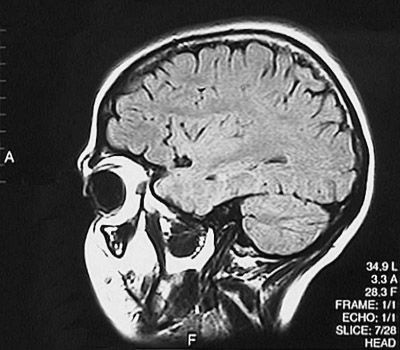

This is a normal sagittal FLAIR MRI scan demonstrating the view to the left of midline at the orbit with the frontal lobe and parietal lobe and occipital lobe and cerebellum and orbit and hippocampus.